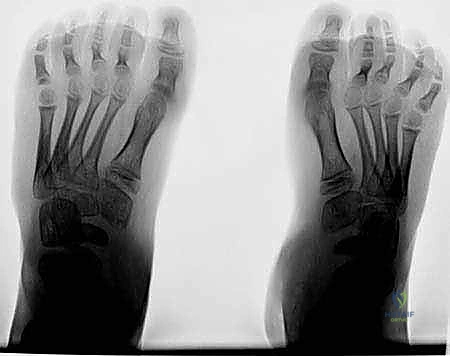

الشكل 1 • تشوهات القدم الجوفاء، منظر جانبي. لاحظ زيادة الانثناء الأخمصي لمقدمة ومنتصف القدم بالنسبة لمؤخرة القدم، وهو ما يسبب ضغطًا هائلاً على مشط القدم.

الشكل 2 • تشوهات القدم الجوفاء، منظر أمامي. يوضح مكونات انقلاب الكعب للداخل وتقوس مقدمة القدم، مما يؤدي إلى عدم استقرار الكاحل.

الأشعة السينية العادية (X-rays) أثناء الوقوف (Weight-bearing) هي الأساس. يقوم الدكتور هطيف بقياس زوايا محددة بدقة هندسية:

* زاوية ميري (Meary's Angle): لتقييم مدى تقوس منتصف القدم.

* زاوية ميل الكعب (Calcaneal Pitch Angle): تكون زائدة بشكل كبير في القدم الجوفاء.

* زاوية هيبس (Hibbs Angle): لتقييم التشوه في مقدمة القدم.